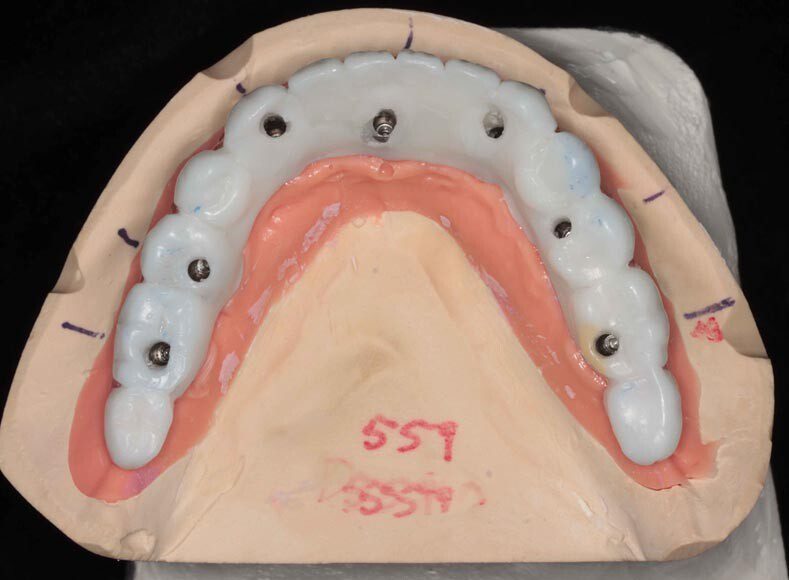

All upper teeth extracted, implants and bone filler placed. Not, we did not remove any bone and attempted to disturb the gums minimally.

Immediate temporary, implant bridge delivered. This is one day post-surgery and delivery of temporary.